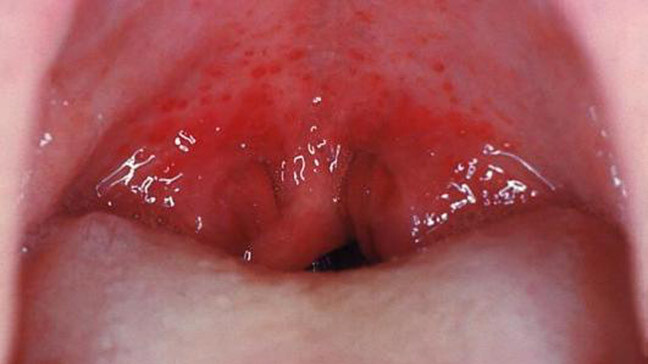

Coxsackievirus

The virus behind hand, foot and mouth disease, coxsackievirus can cause painful blisters and red spots on the roof of the mouth, as well as on the hands and feet. It is most common in children under five years of age, but does occur in people of all ages. Treatment options include over-the-counter medications for fever and pain, as well as special medicated mouthwashes to help alleviate the discomfort associated with the oral sores.